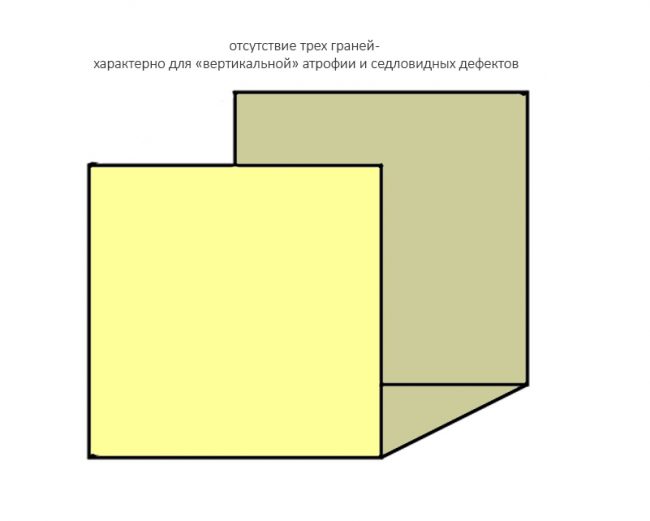

Ну и, отсутствие трех стенок характерно для значительных дефектов кости:

например, для седловидных или т. н. «вертикальных» дефектов:

И крайняя степень — отсутствие четырёх или пяти стенок:

ставит под сомнение целесообразность проведения остеопластики, поскольку добиться качественного результата в таких случаях крайне сложно:

но вполне возможно: